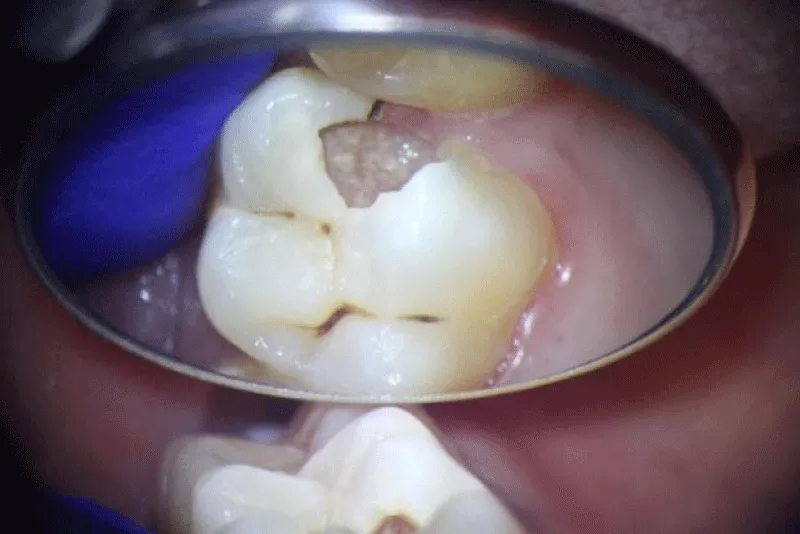

When used strategically, the highest magnification settings of the microscope significantly enhance diagnostic and procedural accuracy. Whether identifying caries, locating canals, or refining tooth preparations, precision and certainty are mandatory. Without proper illumination and magnification, achieving the accuracy required for excellence is nearly impossible [4,5] (Figures 1-3).

Figure 2: Active Cavity, Margins, and Gum Invasion in the Proximal Surface of the Tooth.